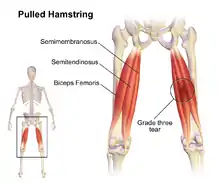

In human anatomy, a hamstring (/ˈhæmstrɪŋ/) is any one of the three posterior thigh muscles between the hip and the knee (from medial to lateral: semimembranosus, semitendinosus and biceps femoris).[3] [4]

The three muscles of the posterior thigh (semitendinosus, semimembranosus, biceps femoris) flex (bend) the knee, while all but the biceps femoris extend (straighten) the hip. The three 'true' hamstrings cross both the hip and the knee joint and are therefore involved in knee flexion and hip extension. The short head of the biceps femoris crosses only one joint (knee) and is therefore not involved in hip extension. With its divergent origin and innervation, it is sometimes excluded from the 'hamstring' characterization.[7]

A common running injury in several sports, excessive stretch of a hamstring results from extensive hip flexion while the knee is extended.[4][8] During sprinting, a hamstring injury may occur from excessive muscle strain during eccentric contraction late in the leg swing phase.[4][8] The overall incidence of a hamstring injury in sports and professional dancers is about two per 1000 hours of performance.[4] In some sports, a hamstring injury occurs at the incidence of 19% of all sports injuries, and results in an average time loss from competition of 24 days.[4]

Imaging the hamstring muscles is usually performed with an ultrasound and/or MRI.[9] The biceps femoris is most commonly injured, followed by semitendinosus. Semimembranosus injury is rare. Imaging is useful in differentiating the grade of strain, especially if the muscle is completely torn.[10] In this setting, the level and degree of retraction can be determined, serving as a useful roadmap prior to any surgery. Those with a hamstring strain of greater than 60mm in length have a greater risk of recurrence.[11]